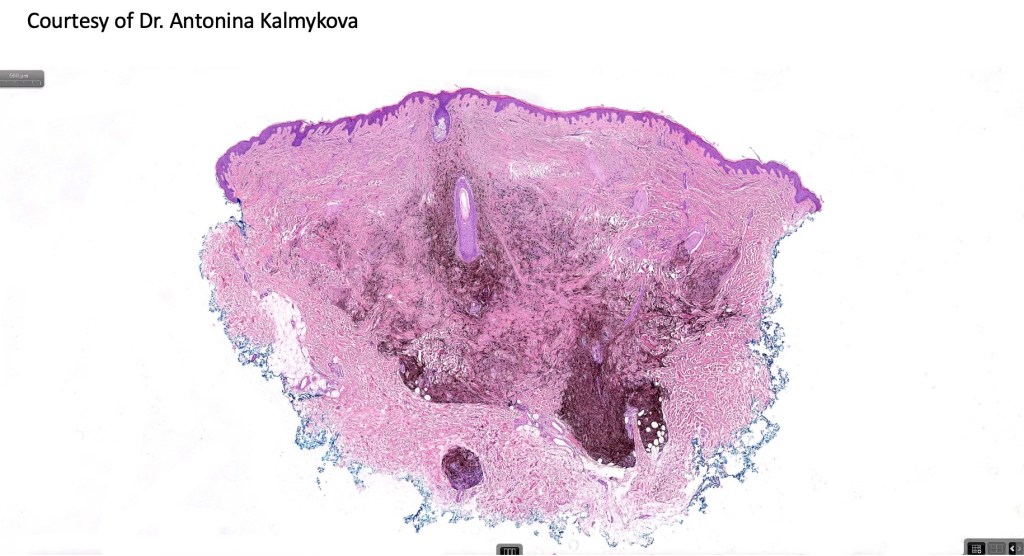

Cellular blue nevus

This uncommon most often devlops on the buttocks, sacrococcygeal region & distal extremities although it may be seen at just about any site. It shows a predilection for females and is diagnosed most often in the 2nd-4th decade. It presents as a blue-black/ or black nodule measuring 1-2 cm in dianeter. Similar to common blue nevus, the cellular variant can be encountered in a wide range of non-cutaneous locations.

•Most characteristic is the dumbbell silhouette although a plague morphology may also be encountered

•Combined nevus variant

•Admixture of spindle cells, pigmented bipolar or dendritic cells & melanophages

•Cytoplasm is pale and nuclei are small with inconspicuous nucleoli

•An alveolar pattern is characteristic particularly with clear cell nodules

•Mitoses are typically very sparse or absent

•No atypical mitoses

•No Necrosis or lymphovascular invasion

•Multinucleate giant cells sometimes present

•Stromal fibrosis, myxoid change, vascular hyalinization with cyst formation are often seen

•Some tumors are composed spindle cells in a fascicular or neuronevoid pattern

•Perineural involvement may be seen

•Balloon cell change

•Desmoplastic variant

•Hypopigmented variant